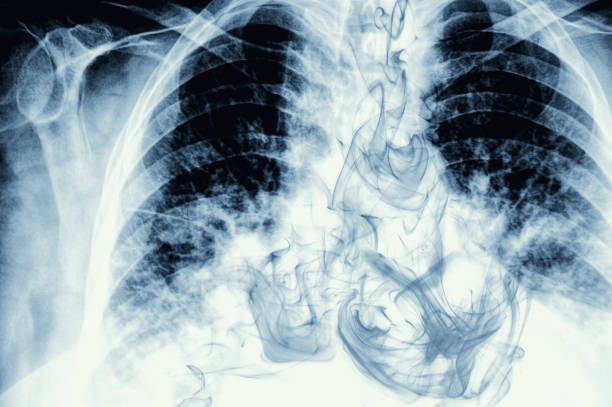

폐암 초기증상 1. 기침

폐암의 가장 흔한 초기 증상은 기침입니다. 그러나 기침의 양상이 다른 증상과 유사하기 때문에 애초에 폐암을 의심하기는 사실 쉽지 않습니다. 따라서 기침 증상에 주의하고 병원에서 치료를 받은 후에도 기침 횟수가 줄어들지 않고 흉통이 지속된다면 폐암의 초기 증상을 의심해 봐야 합니다.. 기침은 폐암 환자의 절반 이상에서 흔한 증상이나 특별한 증상이 아니기 때문에 인식하기 어려우며 특별한 주의가 필요합니다.

폐암 초기증상 2. 흉통

폐암의 초기 증상 두 번째는 기침과 함께 동반되는 흉통이 있습니다. 흉통은 기침으로 인한 것이 아니지만 대부분의 폐암 환자가 호소하는 증상입니다. 흉통은 폐 가장자리의 종양이 흉막과 흉벽에 위치한 암으로 발전하여 흉통이라고 하는 통증을 유발할 때 발생합니다. 기침과 마찬가지로 흉통이 반드시 폐암에 해당하는 것은 아니지만, 폐암으로 인한 흉통은 지속적인 따끔거림과 날카로운 통증을 동반하기 때문에 가슴 부위 통증이 지속되면 기침과 마찬가지로 가족력이 있다면 폐암 검사를 받으실 필요가 있습니다.

폐암 초기증상 3. 쉰 목소리

쉰 목소리도 폐암의 초기 증상 중 하나입니다. 폐암의 초기 증상으로 나타나는 쉰 목소리 역시 반드시 폐암이라고 인식하기 어렵기 때문에 폐암 초기증상으로 나타나는 쉰목소리 역시 무서운 증상입니다.. 반드시 폐암이 아니라 이 증상이 반드시 폐암인 것은 아니지만 목이 쉬는 것이므로 병원에 가서 진찰을 받아야 합니다.

폐암 초기증상 4. 숨가쁨 증상

숨가쁨 역시 폐암의 초기 증상 중 하나입니다. 숨가쁨의 패턴도 다양하므로 만성 폐쇄성 질환(COPD)과 같은 상태로 인한 숨가쁨에 주의해야 합니다. 이로 인한 호흡기능 자체가 저하된다면 향후 호흡기에 의존하여야 하기 때문에 역시 주의가 필요합니다. 숨가뿜 증상의 하나인 만성 폐쇄성 질환(COPD)은 주로 흡연자에게 발생하지만 기도 협착, 폐포폐쇄, 호흡기능 저하 자체가 발생하므로 흡연을 하지 않더라도 COPD가 발생하는 경우에는 COPD 검진 및 조기 치료가 필요하다.

폐암의 초기 증상 5. 객혈

객혈은 또한 폐암의 초기 증상입니다. 암세포가 작아도 기관지를 관통하면 암세포 주변에 수많은 혈관이 생긴다. 폐가 기관지를 자주 자극하면 기침과 가래가 자주 발생하기 때문에 대부분의 폐암 환자들이 통증을 호소하는 것으로 알려져 있다.

폐암 초기증상 6. 체중감소

체중 감소 역시 폐암 초기 증상 중 하나입니다. 체중감소는 암세포에 의한 거식증으로 인해 기면증과 급격한 체중감소의 증상이 있거나 단순 체중감소 증상이 있다면 폐암이 아니더라도 '암'을 의심해야하는데 이는 암세포가 아무래도 우리 체내에서 신진대사에 영향을 미치기 때문에 체중감소가 지속되면 반드시 병원진료를 받으셔야 합니다.

폐암 초기증상 7. 상대정맥증후군

상대정맥증후군 역시 폐암의 초기증상 중 하나입니다. 상대정맥증후군은 폐암이 상대정맥 주위에 발생하여 상대정맥을 압박하여 순환장애, 머리와 팔 등 신체 여러 부위의 부종, 호흡곤란, 흉부정맥 탈출 등으로 발생합니다.

폐암 초기증상 8. 두통

두통은 또한 폐암 초기 증상 중 하나입니다. 암세포의 가장 무서운 점은 암세포가 체내에 다른 기관으로 전이된다는 것입니다. 폐에 상존하는 암세포라도 뇌로 전이될 가능성이 높아 혈관에 압력을 가하고, 두통이 생기면 메스꺼움이 생겨 두통을 유발하기 때문에 절대로 가볍게 지나치지 말고 두통이 심하다면 별다른 원인을 찾지 못하고 있다면 폐암과 관련된 증상도 확인한번 하시기 바랍니다.